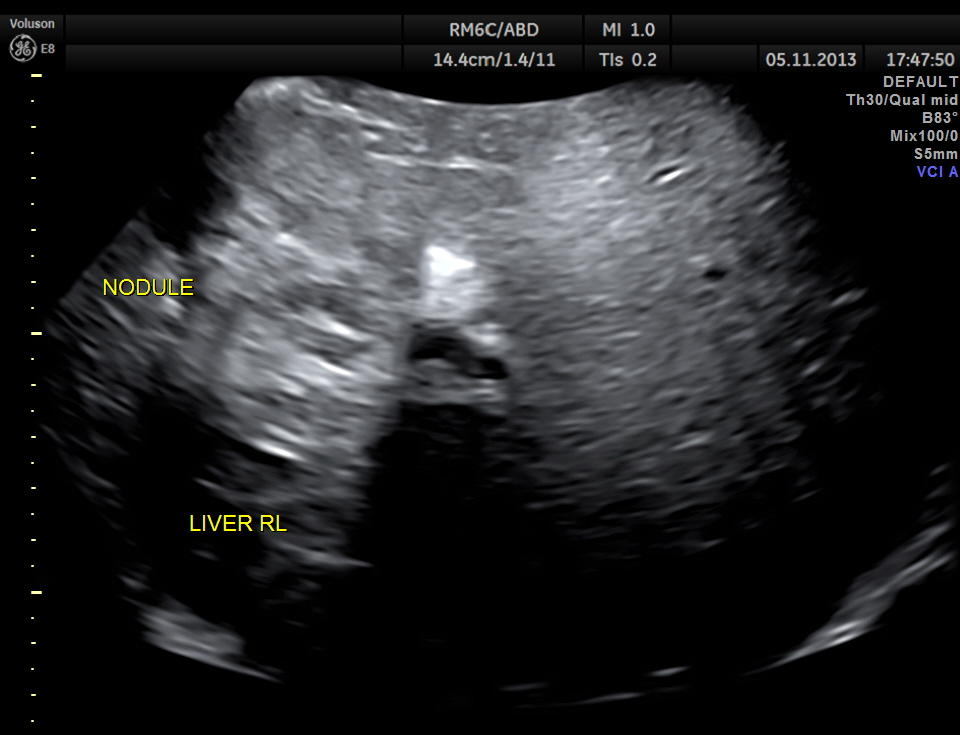

Volume contrast imaging ( VCI – A plane of the liver nodule )

This patient had a painful metastatic nodule in the right lobe of the liver. He also had loculated sub diaphragmatic collection and a septated cystic mass in the free surface of the liver.